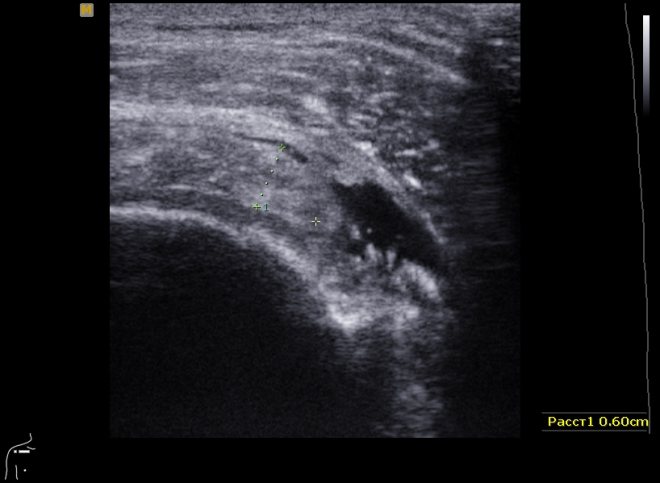

Во время УЗИ врач устанавливает датчик на кожу в проекции той части тела, которая подлежит осмотру. Датчик испускает ультразвуковой сигнал и регистрирует ответ тканей на него. При компьютерной обработке отраженного сигнала на экране аппарата формируется изображение в режиме текущего времени. Врач оценивает это изображение, проводит необходимые замеры.

С помощью УЗИ плечевого сустава можно обнаружить признаки заболеваний, травм, врожденной патологии мягких тканей, связок, хрящей и других структур. Врач, проводящий УЗ-диагностику, кроме общего осмотра, производит несколько замеров и регистрирует полученные результаты в протоколе. Перечень структур и их характеристики, которые должны отражаться в протоколе, стандартны. Протокол имеет паспортную, описательную часть и заключение.

Как видны патологии сустава на УЗИ

При заболевании сустава или его травме структуры, оцениваемые при УЗИ, выглядят иначе, чем в норме. Может выявляться изменение толщины синовиальной оболочки, повышение или снижение эхогенности тканей (показатель их плотности), увеличение объема жидкостного компонента, нарушение анатомических соотношений и другие отклонения.